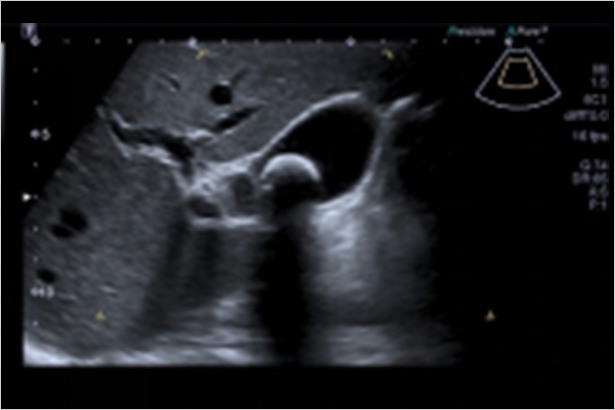

可同時顯示大血管內血流方向信息以及微灌注信息

超聲造影定量和分析工具(如 CHi-Q 組件)幫助排除呼吸運動干擾,提高準確性、一致性以及檢查速度